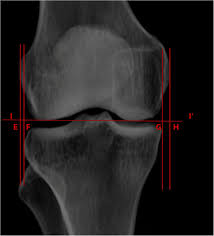

Medial condyle of femur from wikipedia, the free encyclopedia the medial condyle is one of the two projections on the lower extremity of femur, the other being the lateral condyle. The lateral condyle was involved in 44 % and the medial condyle in 12 %. Palpable as a hard, rounded bump to the inside of either knee joint, they are one of two condyles at the bottom of each leg bone, the other being the lateral femoral condyle. This adaptable graft option is most commonly used with oats or shell techniques to restore cartilage in the knee, but can also be used to for cartilage restoration of other joints. In a review of 79 patients with this disease, performed to establish guidelines f … The medial femoral condyle is supplied by a plexus of vessels from the descending genicular artery and the medial superior genicular artery. The medial condyle is larger than the lateral (outer) condyle due to more weight bearing caused by the centre of mass being medial to the knee. Root tear (radial tear) of the medial meniscus mild or moderate knee arthritis According to the hospital for special surgery, the medial femoral condyle is the inside of the knee, and health issues dealing with it can be treated. Osteonecrosis of the medial femoral condyle can be treated in a variety of ways depending on the stage of the disease. The medial condyle is named for its location on the inside of the knee, closer to the midline of the body, while the lateral condyle is found on the outside of the knee, away from the midline of the body. In the knee, chondromalacia is usually related to injury, overuse of the knee, and poorly aligned muscles and bones around the knee joint. Your knee mri will often show a:

Of the six patients who had suffered an isolated fracture of their medial condyle, four of the patients had their fractures diagnosed on the first visit. The lateral condyle was involved in 44 % and the medial condyle in 12 %. It acts to support a significant amount of the patient's body weight. Cartilage can be focally damaged, producing a pot hole in the joint surface, when the knee ligaments are injured. Osteonecrosis of the medial femoral condyle presents as a sudden onset of pain on the medial side of the knee. A bone fracture at this location is termed a femoral condyle fracture. The femoral condyle is a thickened area of the femur just above the knee. One presumed mechanism of injury is a stieda fracture (avulsion injury of the medial collateral ligament at the medial femoral condyle). Root tear (radial tear) of the medial meniscus mild or moderate knee arthritis Coronal plane fracture of the lateral femoral condyle. The lesions were located on the medial femoral condyle in 8 (72.7%) cases and on the medial tibial plateau in 3 cases (27.3%). The medial femoral condyles are the bony protrusions on the inside edge of the bottom of the femur bone in each thigh. Based on the patient's antalgic gait and radiographic findings, the patient was instructed on the proper use of crutches and referred to an orthopaedic surgeon for appropriate management.

Methods sixteen knees with a small medial femoral. The lesions were located on the medial femoral condyle in 8 (72.7%) cases and on the medial tibial plateau in 3 cases (27.3%). Radiographic features it is almost always unilateral, usually affects the medial femoral condyle (but can occasionally involve the tibial plateau 9) and is often associated with a meniscal tear. In the knee, chondromalacia is usually related to injury, overuse of the knee, and poorly aligned muscles and bones around the knee joint. It acts to support a significant amount of the patient's body weight. Normal irregular ossification of the femoral condyles was present in 66% of the boys and 44 % of the girls 1 in a review of knee radiographs of 147 healthy, asymptomatic children between the ages of 3 and 13 years. The inner side of the knee or the medial femoral condyle is the most common area for a cartilage defect. A bone fracture at this location is termed a femoral condyle fracture. Palpable to either side of the knee joint when it is bent, they are known specifically as the medial and lateral femoral condyles. If there is a fracture (break) in part of the condyle, this is known as a fracture of the femoral condyle. Primary osteonecrosis of the femoral condyle shares several features with insufficiency fractures, including predominance in elderly women with factors responsible for mechanical stress (varum, obesity, trivial trauma), mechanical pain, and increased radionuclide uptake. An imbalance of the muscles around the knee (some muscles are weaker than others.) overuse (repeated bending or twisting) of the knee joint, especially during sports. Sagittal plane fracture of the medial femoral condyle.